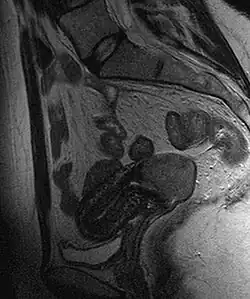

La clasificación de las etapas clínicas de la evolución del carcinoma de cuello, partiendo de la etapa cero, que correspondería al carcinoma in situ (CIN-III o HSIL):[6]

- Estadio I: confinado al cuello del útero. Con un estadio IA si el tumor mide menos de 7 mm de superficie y 5 mm de invasión en profundidad; y un estadio IB si el tumor mide más o es macroscópico.

- Estadio II: se extiende más allá del cuello, pero no se extiende a la pared de la pelvis y, si afecta a la vagina, no llega a su tercio inferior. Se clasifica como IIA si no afecta a parametrios (IIA1 si es menor de 4 cm y IIA2 si es mayor) y IIB si los afecta.

- Estadio III: el carcinoma se extiende a la pared pelviana. En la exploración al tacto rectal no existe espacio entre el tumor y la pared pelviana; el tumor se extiende además al tercio inferior de la vagina. Sería un estadio IIIA si afecta al tercio inferior de la vagina, y un IIIB si afecta pared pélvica o tiene repercusión sobre el riñón.

- Estadio IV: estadio metastásico local (puede infiltrar la pared de la vejiga urinaria o el recto) (IVA) o a distancia (IVB), por ejemplo si aparecen en los pulmones.